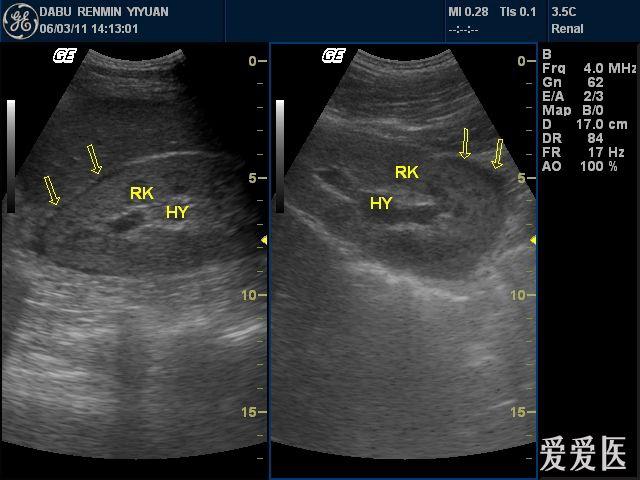

第一节 肾积水-腹部彩色超声诊断-医学

图片尺寸976x737

左肾积水 ↑ 左侧输尿管扩张,中段可见结石

图片尺寸829x621